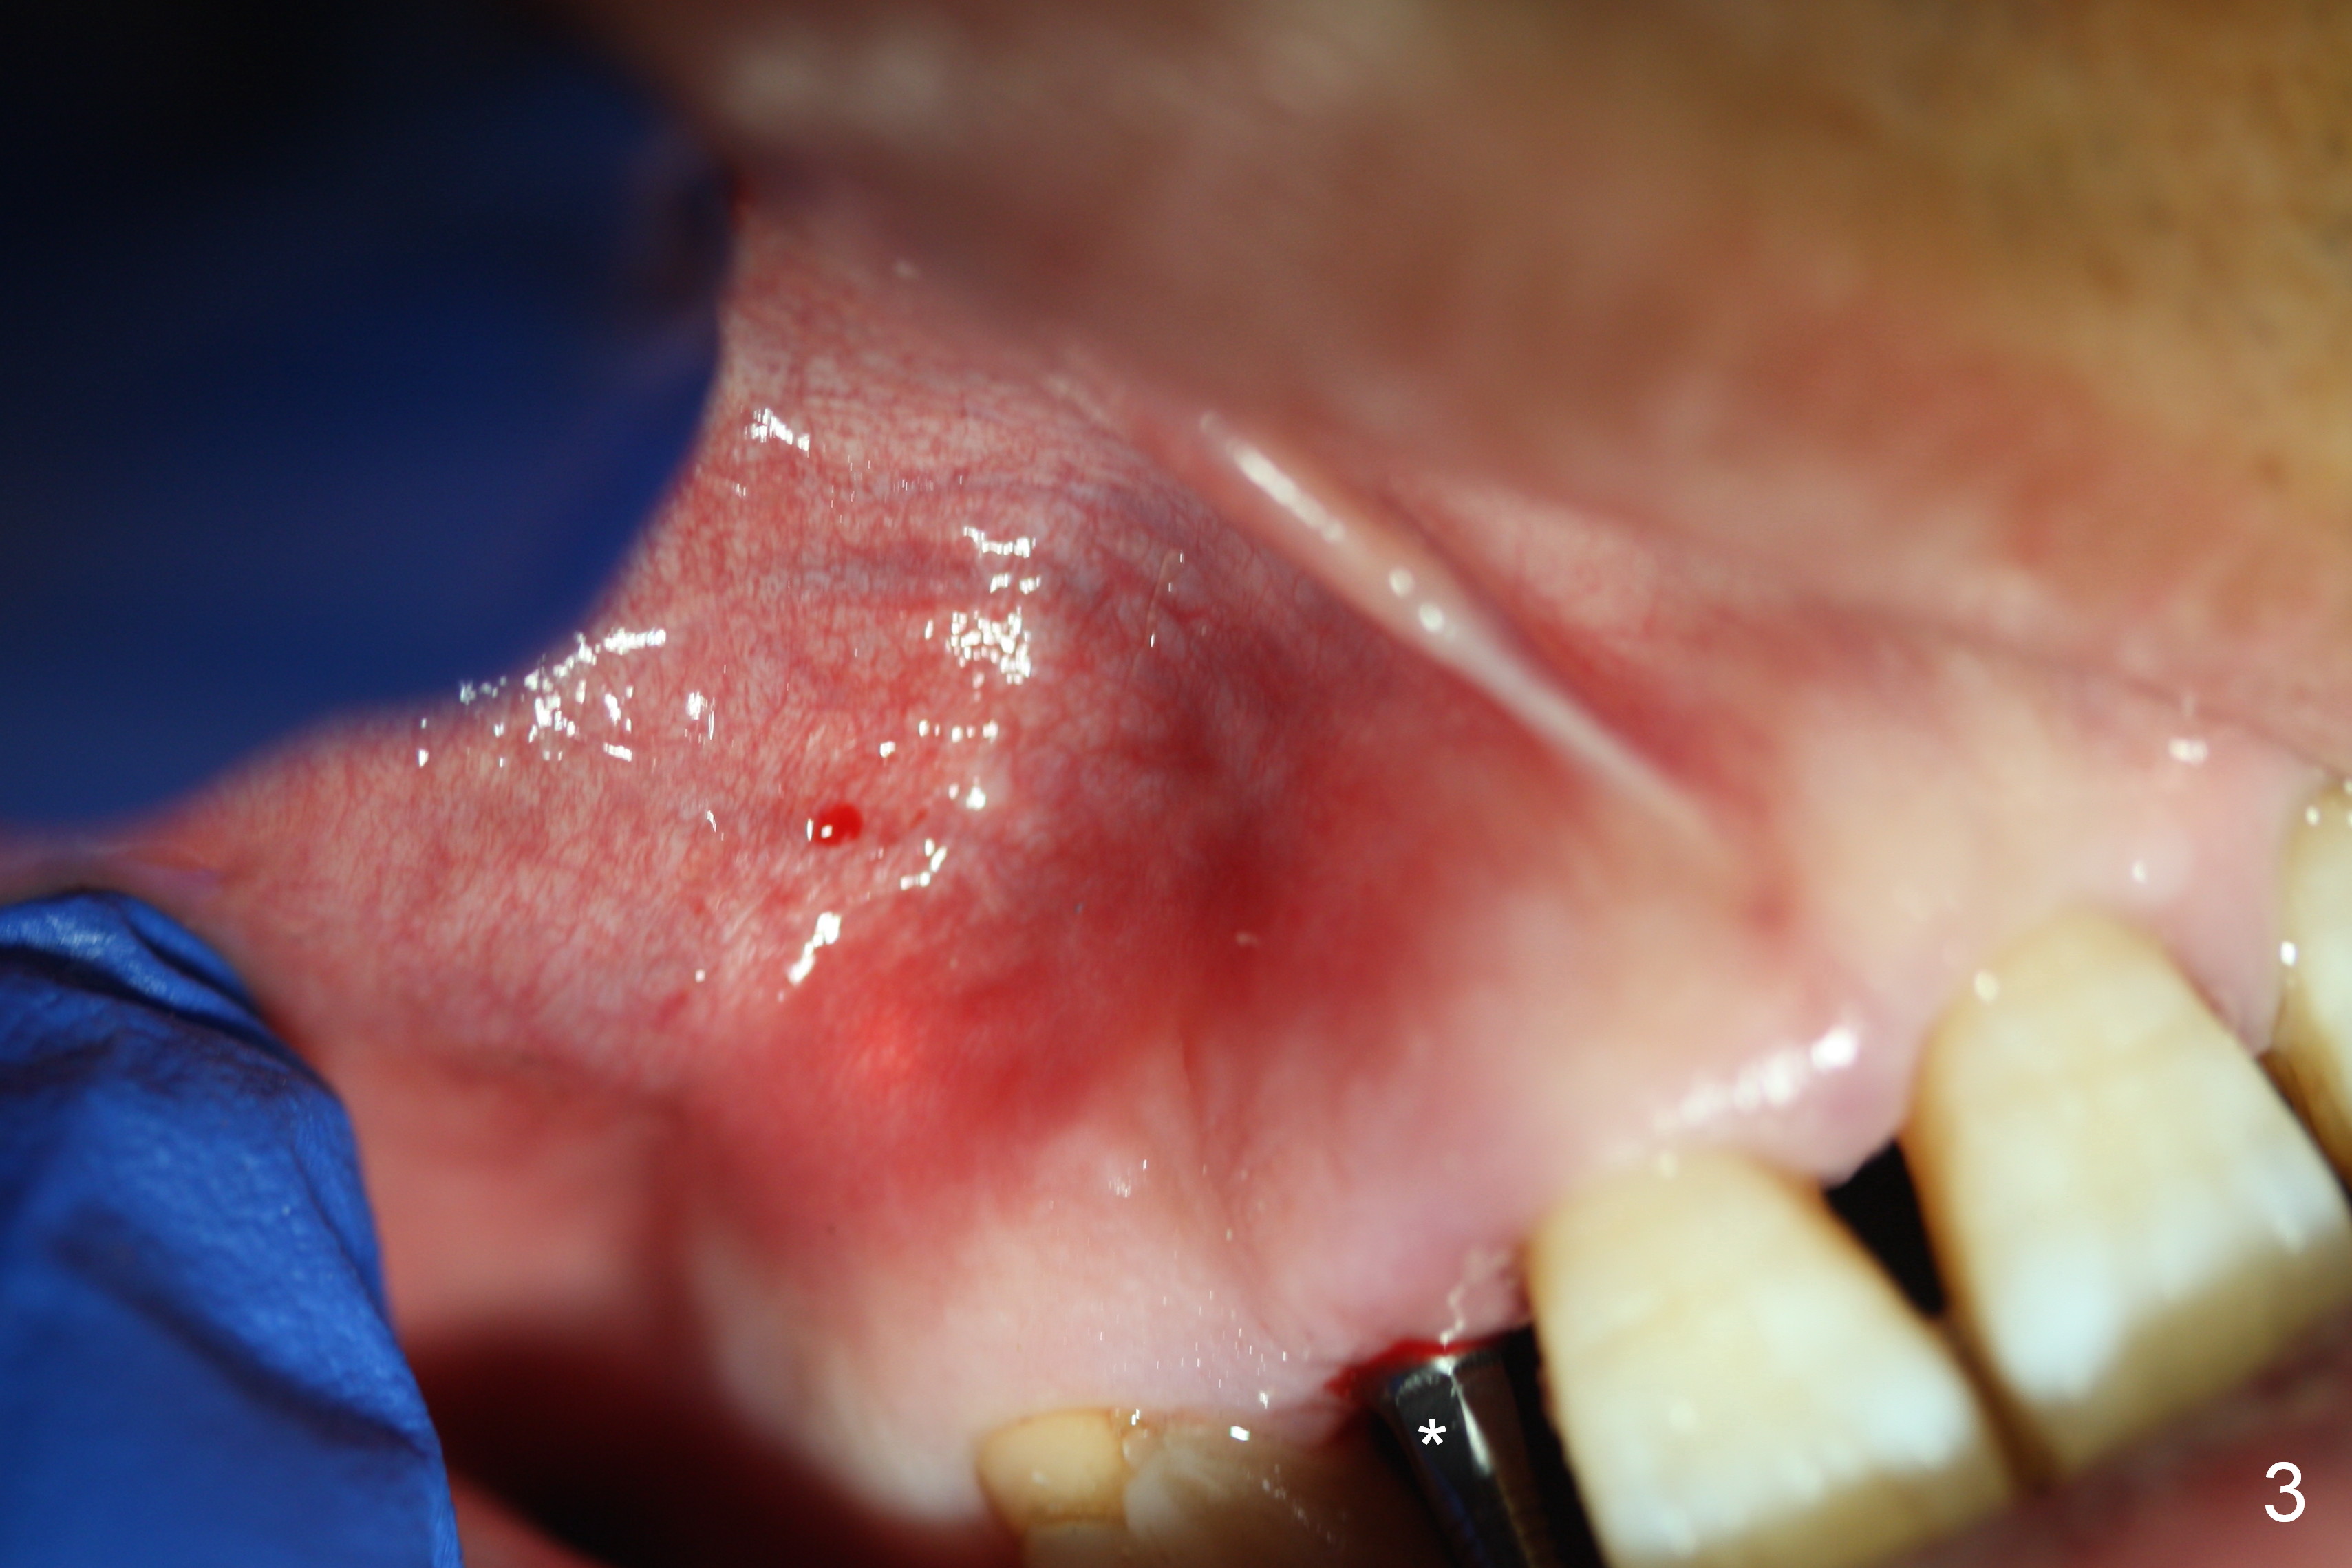

Preop exam shows the apparent wide ridge at #7 (Fig.1). What is ignored preop is the concavity in the apical buccal region (Fig.2 *). When a 3x16(4) mm 1-piece implant is being placed (Fig.3 *, flapless), the apical buccal plate vibration is felt. The biggest mistake is that initial osteotomy is ~ 6 mm shy of the implant length, partially because of 6 mm gingival height. Since the tooth #6 is symptomatic after RCT with paste overfill (Fig.4 >), apicoectomy is contemplated at #6 with exploration of the buccal plate at #7 (Fig.5). Since the implant appears to be long enough, implant apical resection is performed (Fig.6). Since there is coronal thread exposure due to previous periodontitis (Fig.7 <), bone graft is placed in these 3 defective areas after decortication.